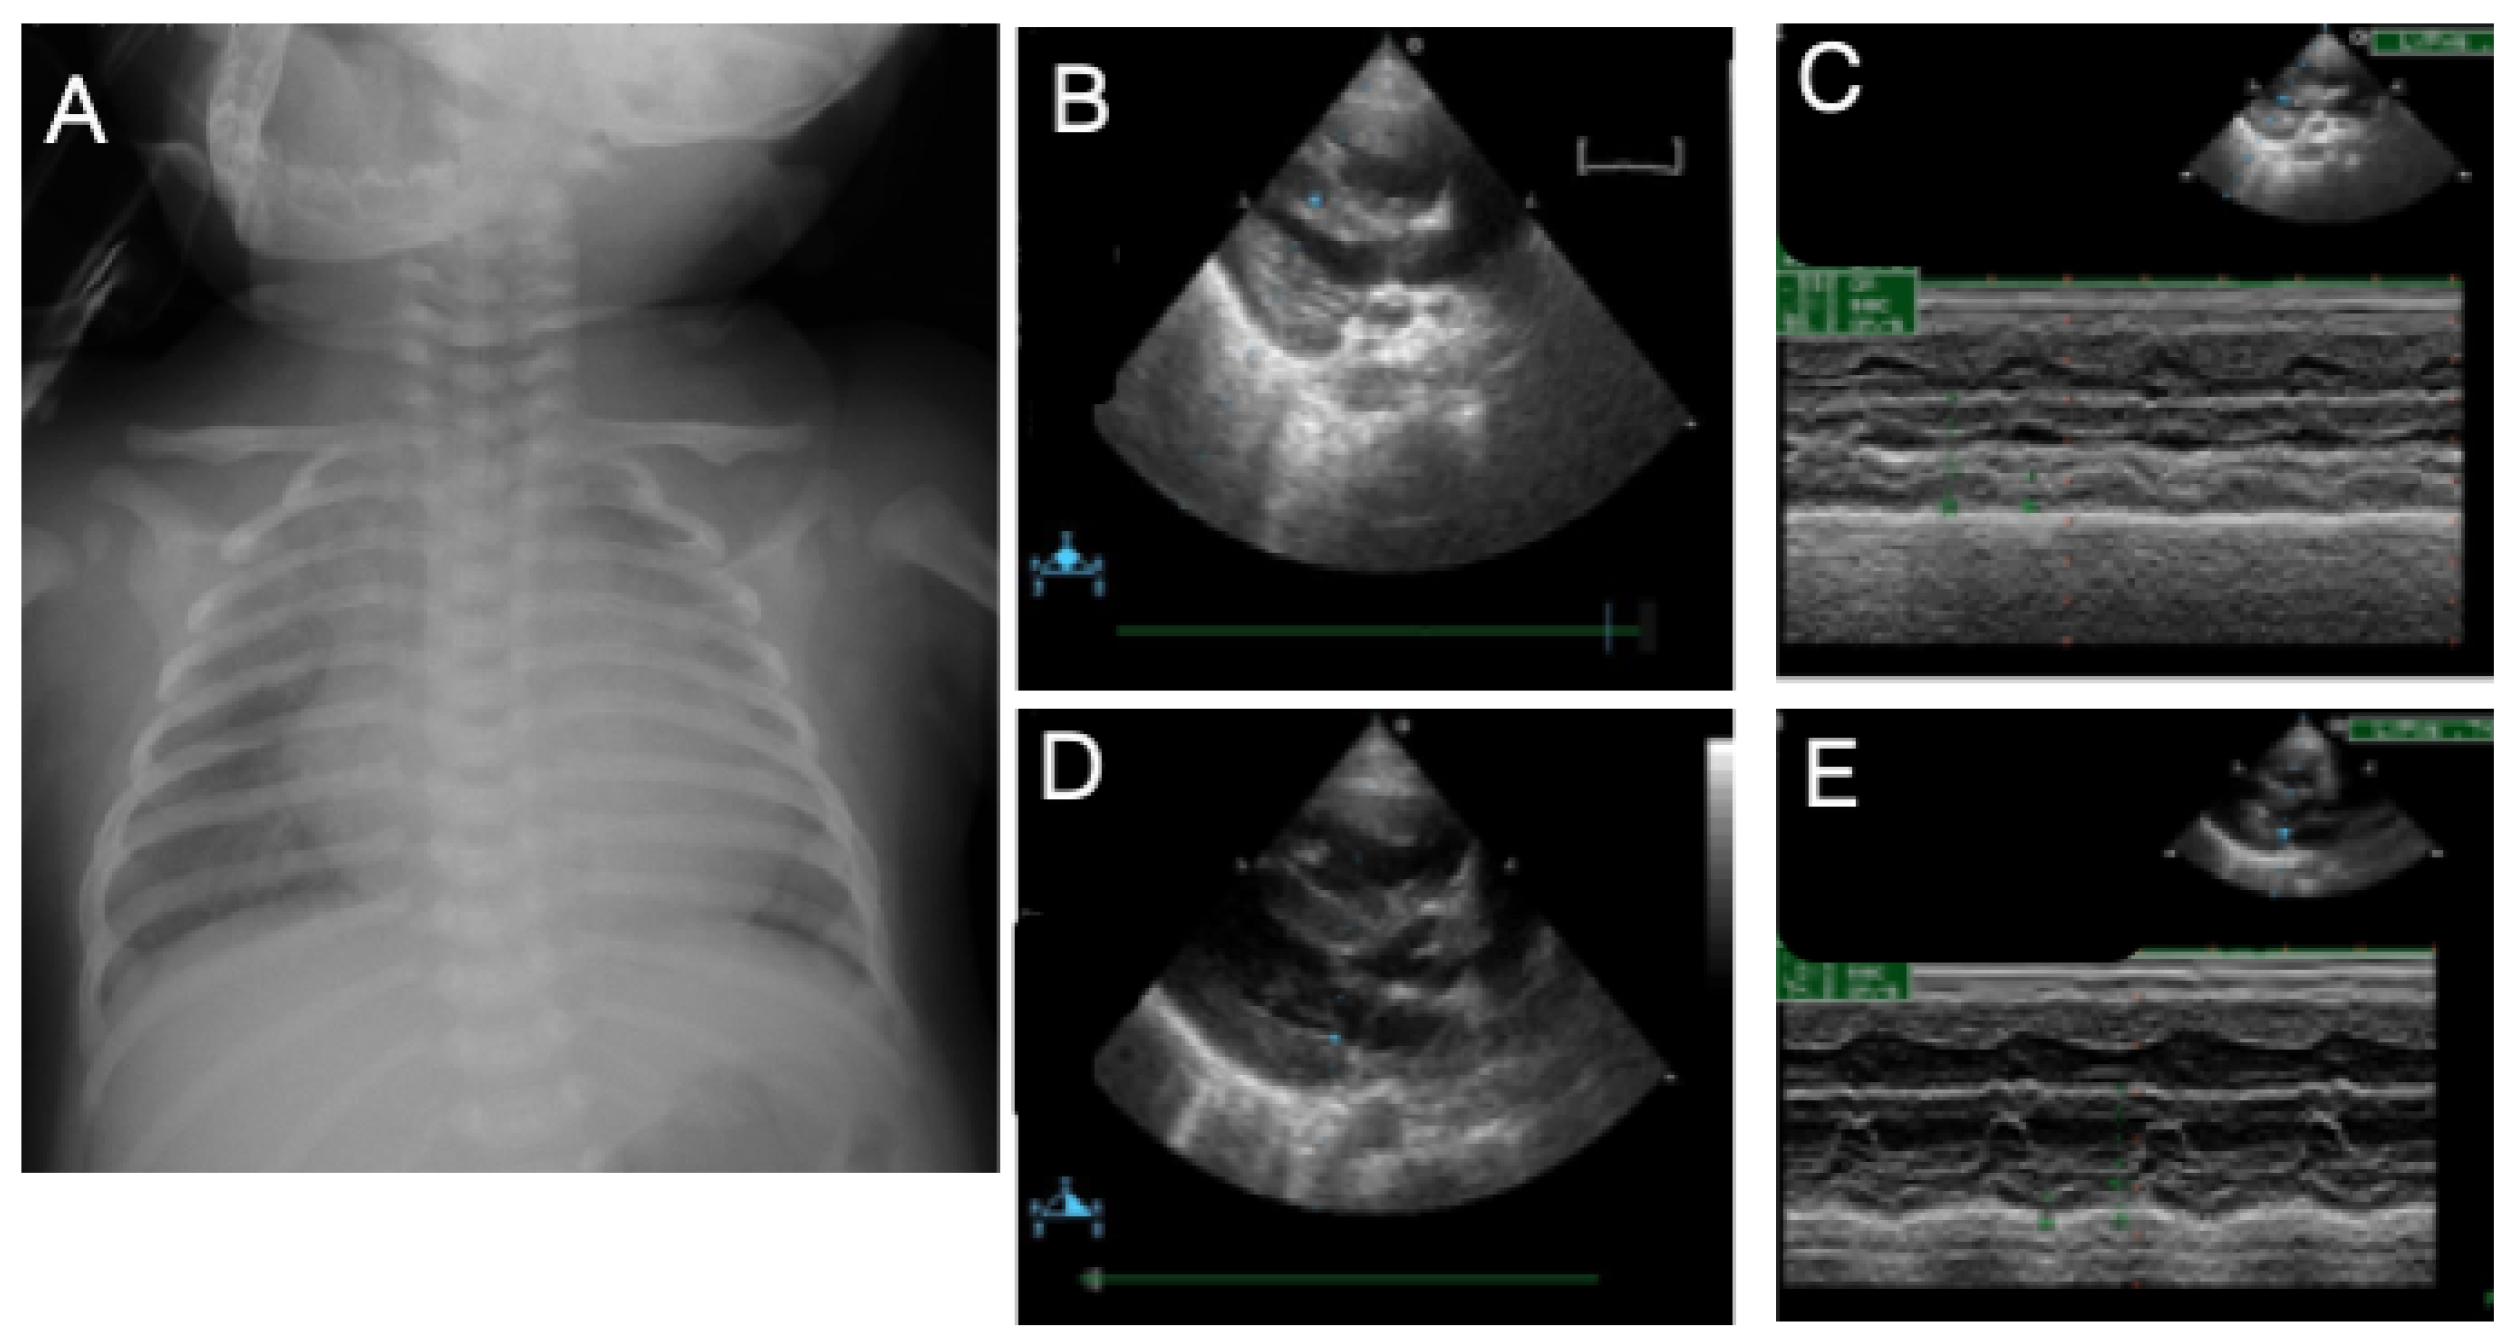

3.5. Case 5

3.6. Case 6